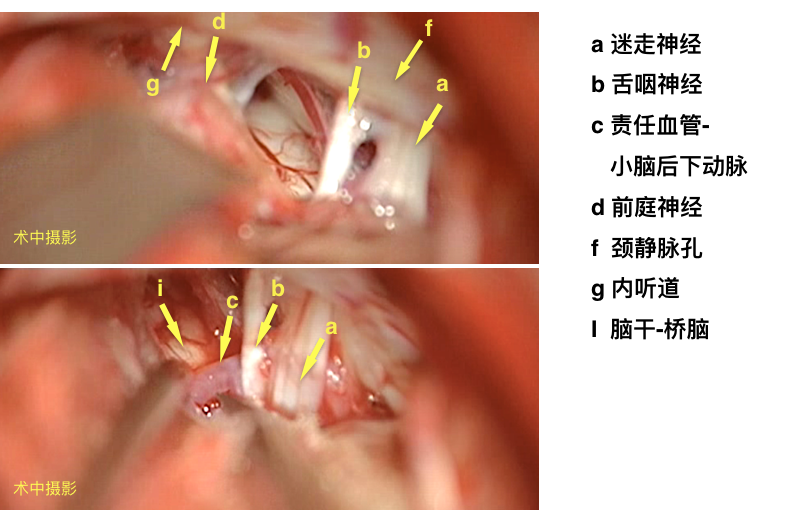

电生理辅助枕下乙状窦后入路显微血管减压术。

手术录像

面肌痉挛常可见动脉压迫面神经根部或压迫面听神经复合体,本病例MR阴性,术中探查亦未见直接神经的责任血管,电生理监测下判断责任血管,为压迫面神经根部腹侧脑干的小脑后下动脉。